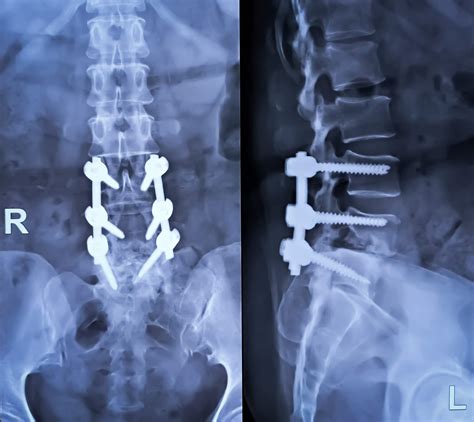

Anterior Lumbar Fusion Disc Replacement - Comprehensive MD